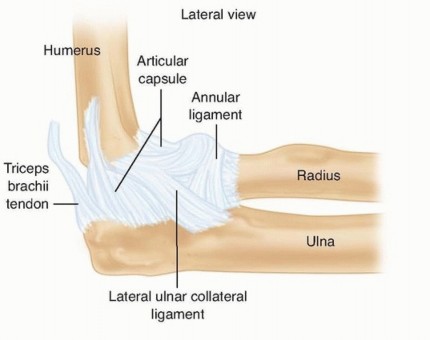

DEFINITION Simple dislocations of the elbow can most often be treated successfully with closed means: reducti…